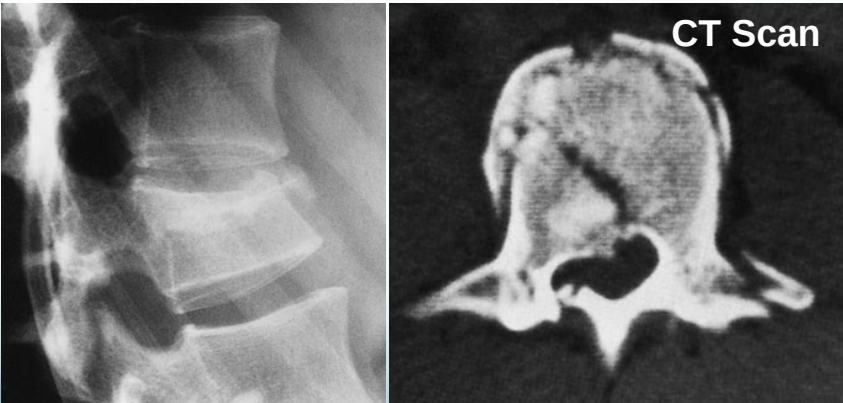

Burst Injury L-Spine

- Axial compression: shattered vertebral body

- Posterior fragments into spinal canal

- Usually unstable

- CT required

Burst Injury Classification

Is this a compression or a burst fracture?

- A burst fracture

- Why?

- Posterior displacement